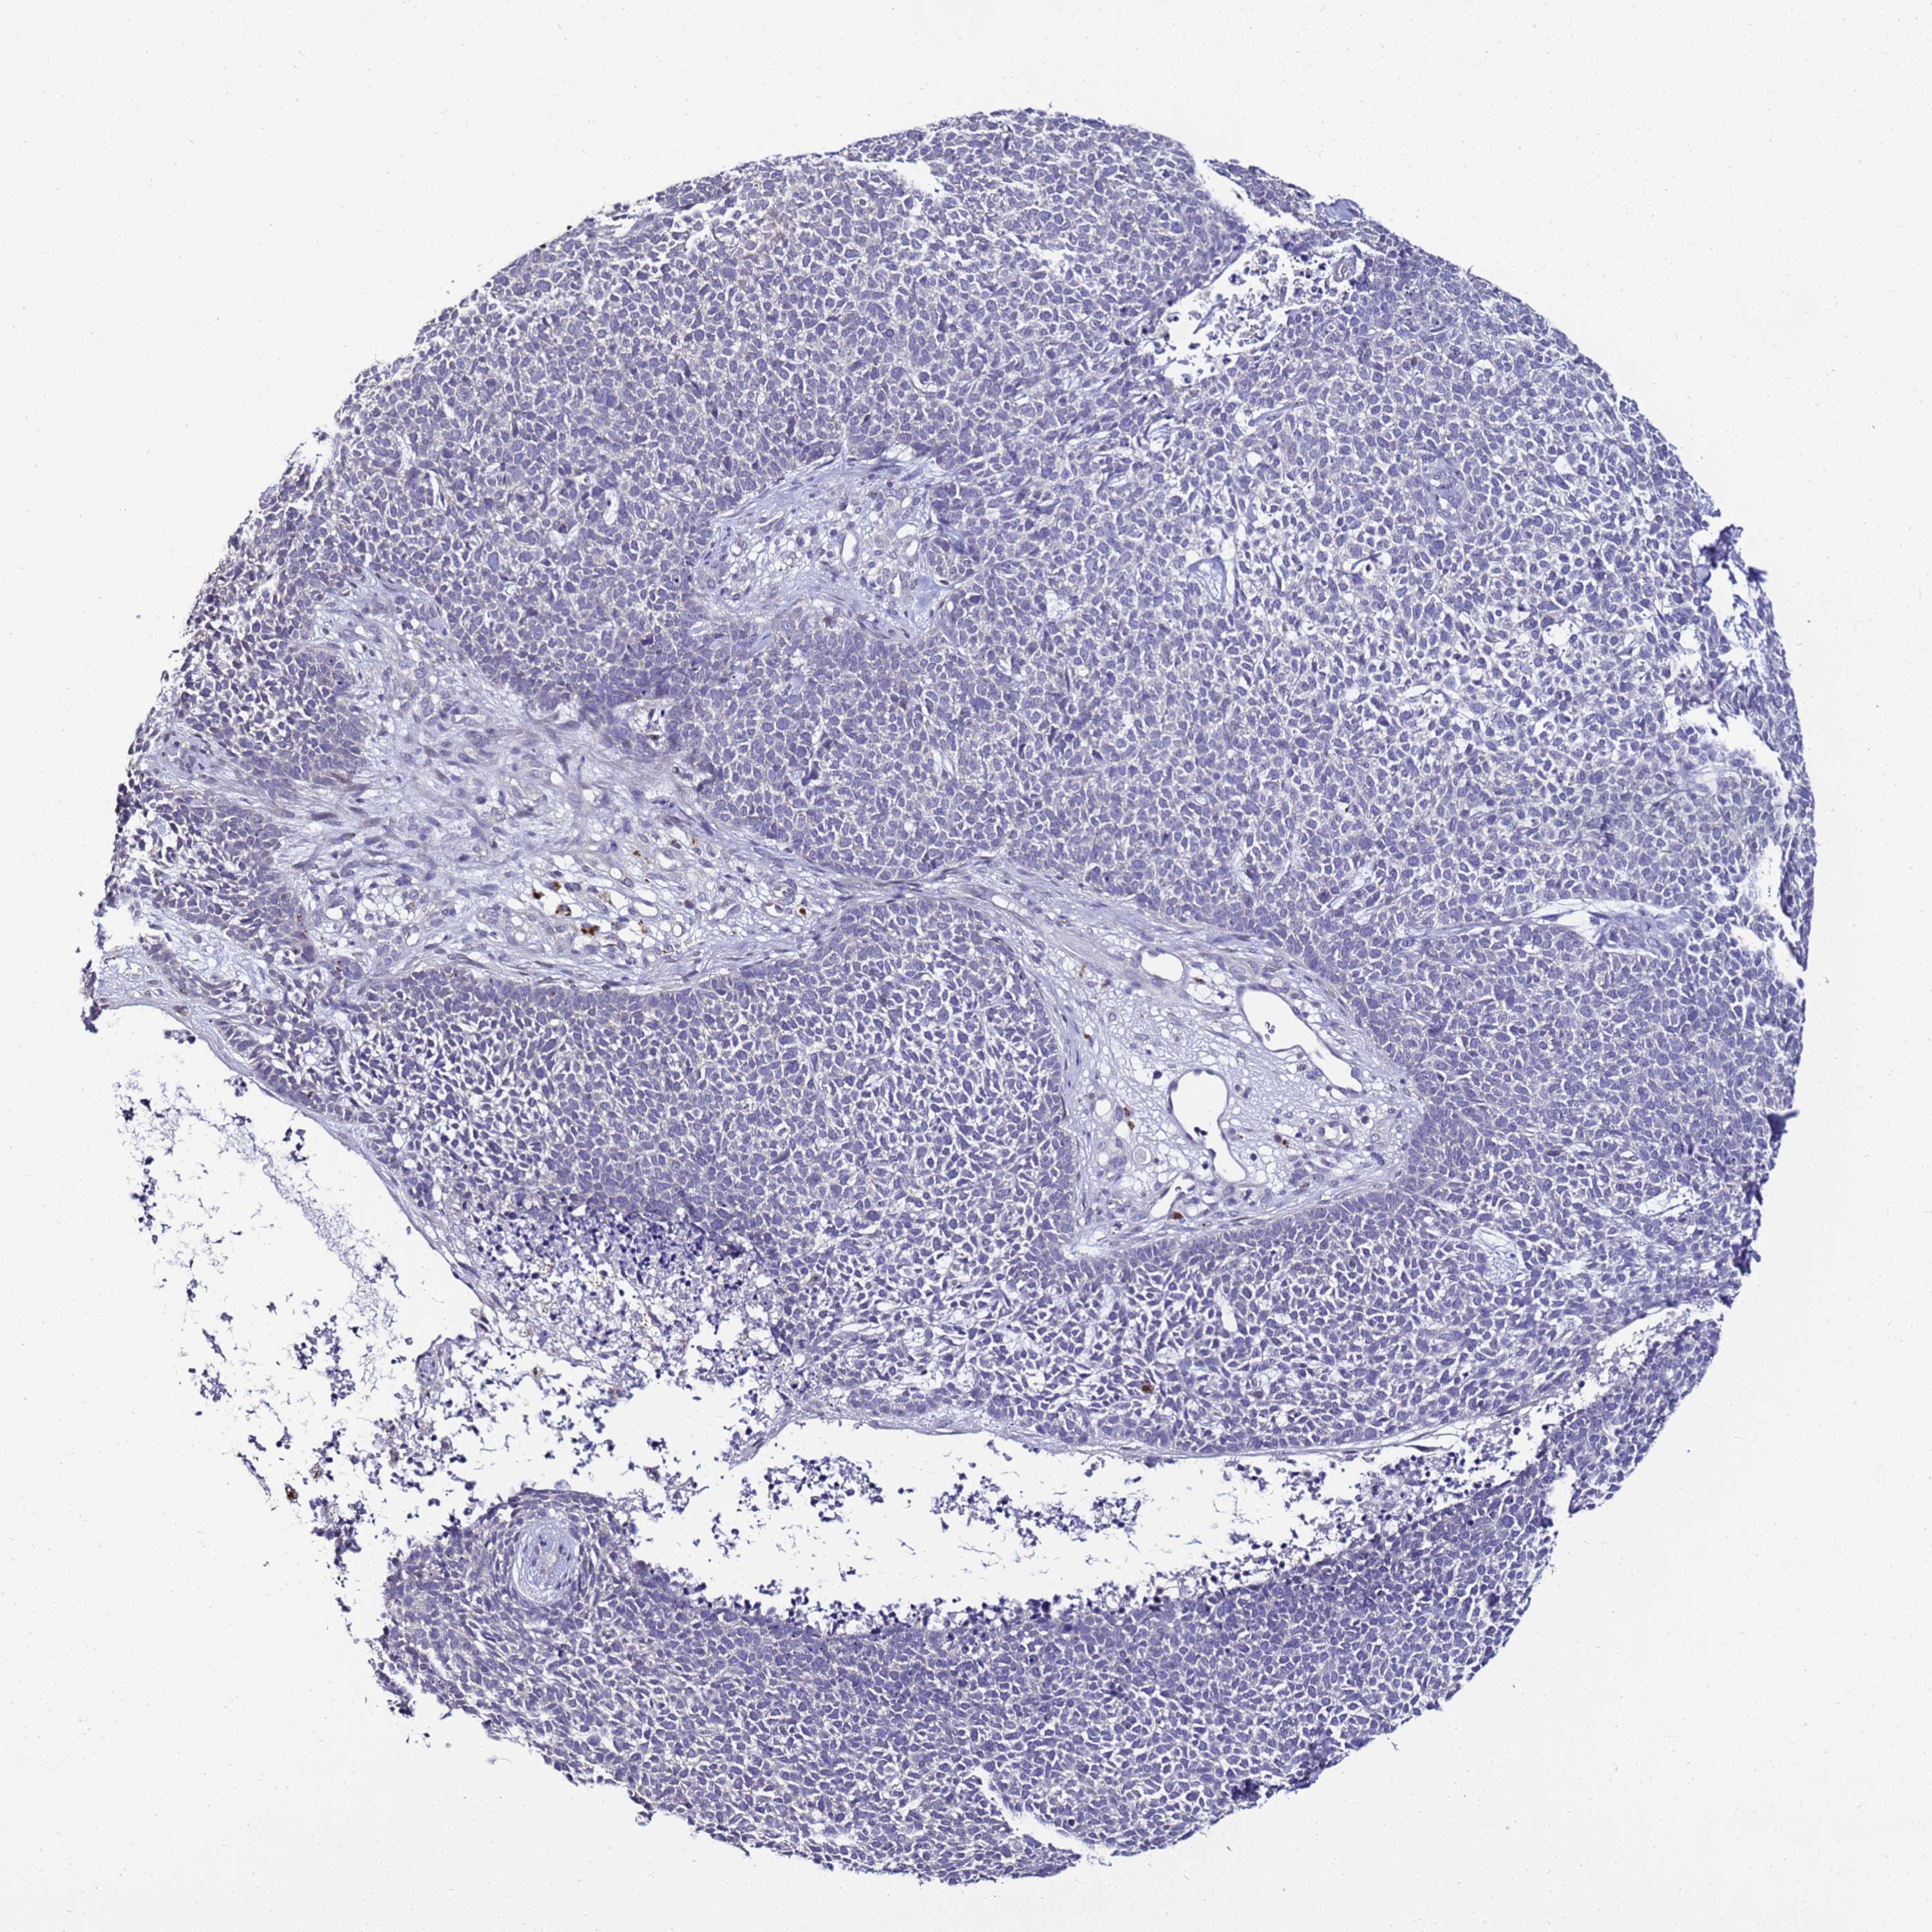

Basal cell and squamous cell cancer

SKIN CANCER - Protein expressioni

A mouse-over function shows sample information and annotation data. Click on an image to view it in a full screen mode. Samples can be filtered based on level of antibody staining by selecting one or several of the following categories: high, medium, low and not detected. The assay and annotation is described here.

Each image is clickable and will lead to virtual microscopy that enables deeper exploration of all samples and also displays staining intensity scores, fraction scores and subcellular localization as well as patient and tissue information for each sample.

Antibody HPA045540

Squamous cell carcinoma, NOS

Squamous cell carcinoma, metastatic, NOS